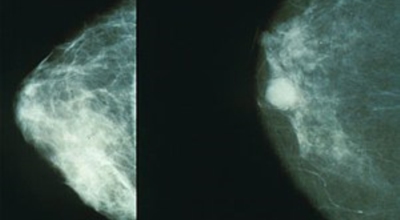

보통 자신의 인체사이즈 가슴의 크기가 빠르게 변화하지는 않아요. 또한 좌우가 완벽하진 않습니다. 하지만 대체적으로 대칭에 가까운 밸런스를 지속시켜니다. 그러나 초기증상이 나타나게 되면 한쪽 가슴이 유독 부풀거나 및 가슴 형태가 조금은 예전과는 다르고 다른 한쪽과 다른 느낌이 든다면 초기증상일수 있다고 합니다.

유방암 초기증상 - 유방의 혹

보통 응어리가 잡히는 분들의 40%는 물혹으로 가벼운 질병으로 바로 치유가 되는 경우가 많은데요 20~30%의 확률로 유방암일 가능성이 있다고 합니다. 따라서 매일같이 자신의 가슴을 마사지 해주시다 어느날 응어리가 잡히게 된다면 유방암 검사 초기에 받아 보시기를 권해 드려요.